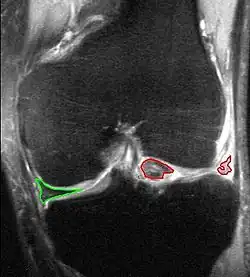

Bucket-handle tear of the lateral meniscus (red). Medial meniscus intact (green). MRI, coronal T2 *-weighted GRE sequence.

X-ray images (normally during weightbearing) can be obtained to rule out other conditions or to see if the patient also has osteoarthritis. The menisci themselves cannot be visualised with plain radiographs. If the diagnosis is not clear from the history and examination, the menisci can be imaged with magnetic resonance imaging (an MRI scan). This technique has replaced previous arthrography, which involved injecting contrast medium into the joint space. In straightforward cases, knee arthroscopy allows quick diagnosis and simultaneous treatment. Recent clinical data shows that MRI and clinical testing are comparable in sensitivity and specificity when looking for a meniscal tear.